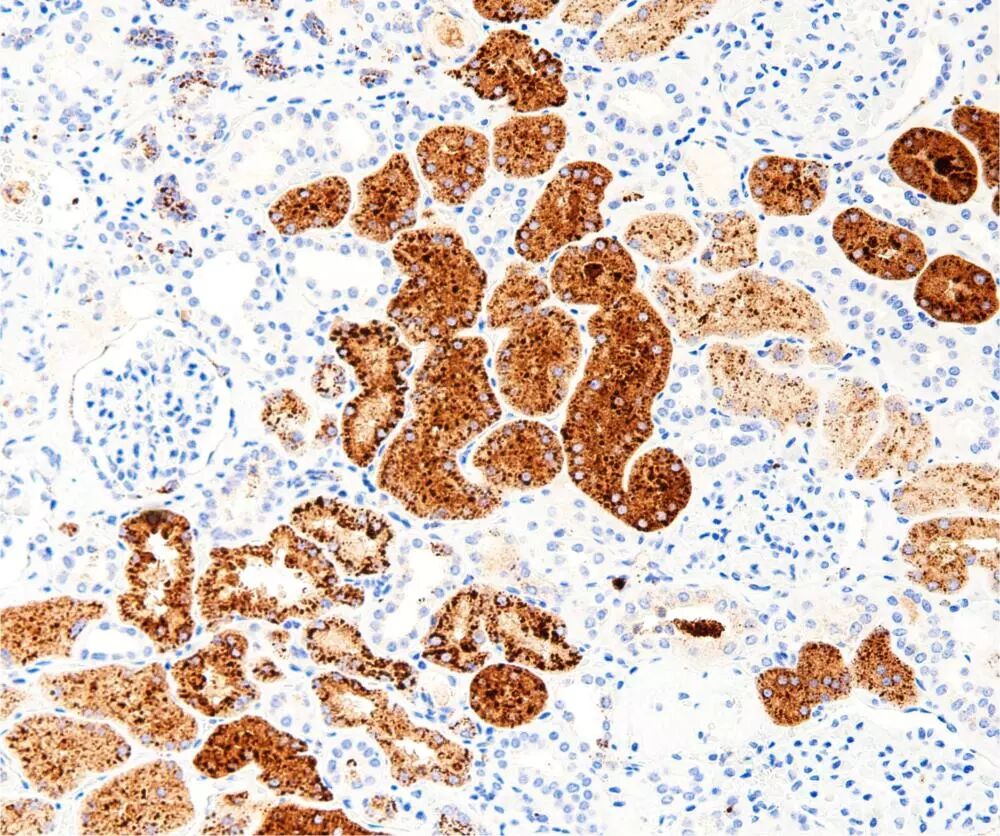

CD56 (clone: C5A2)

CD56属于细胞表面糖蛋白,是一种神经细胞黏附分子,也是NK细胞的标志物。在胚胎发生发育以及神经细胞的相互联系中发挥重要的作用。CD56在癌症侵袭性研究过程当中也具有重要的意义。其主要表达于神经元、星形细胞、施万细胞、NK细胞和小部分活化的T淋巴细胞。

CD56主要在肺小细胞癌、间皮瘤、类癌、胰岛细胞肿瘤、有神经内分泌分化的胰腺肿瘤、Merkel(梅克尔)细胞癌、肝细胞癌、部分肾细胞癌、部分卵巢癌、部分子宫内膜癌、甲状腺滤泡和乳头癌、神经母细胞瘤、神经节胶质瘤、少突神经细胞胶质瘤、视网膜母细胞癌、NK大颗粒淋巴细胞白血病、骨髓瘤和肝脏的窦组织细胞中有表达。

CD56在鼻咽癌、黑色素瘤、脑膜瘤、结肠癌、滤泡中心细胞淋巴瘤、毛细胞白血病和Ewing肉瘤中不表达。

阳性部位:胞质/胞膜